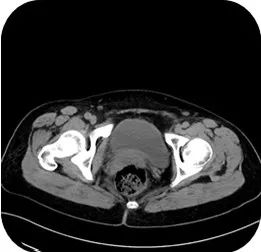

肝胆胰脾肾CT:肝囊肿;肝内钙化灶;胰腺形态饱满。